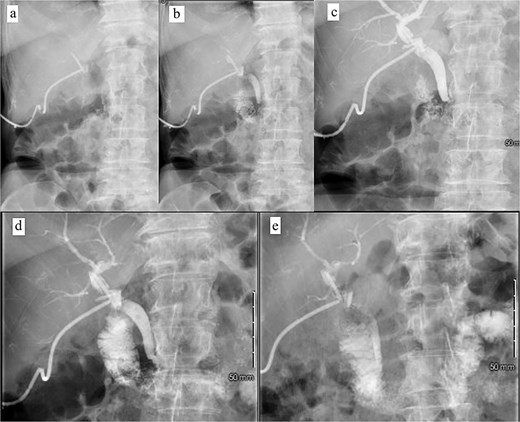

Patient was discharged home on POD 7 following IV antibiotic completion (Fig. 5). Patient was seen in the ER 1 week later for drainage around the T-tube. Tube study confirmed resolution of CBD obstruction and the patient was discharged from the ER (Fig. 6).

Postoperative tube study in ER. (a) Contrast injected into the cholecystostomy tube. (b) Contrast entering the CBD. (c) Contrast completely filling the CBD and intrahepatic ducts. (d) Contrast leaving the CBD and into the duodenum. (e) Contrast predominately in the small bowel.